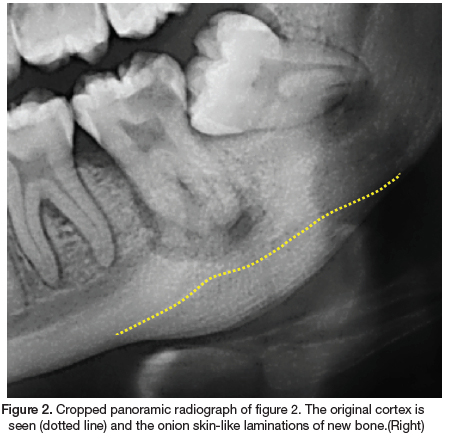

A 22-year-old female presented to our clinic with the main complaint of pain and swelling in the left mandible. The medical history revealed no co-morbidities. Extraoral examination revealed a draining sinus and a hard, firm swelling in the posterior left mandible. Intraoral examination revealed multiple carious teeth and healthy overlying mucosa. A panoramic radiograph was performed (Figure 1). Radiographic examination revealed a missing 18, impacted 28, 38, 48 and carious lesions on the 17, 15, 37 and 36. A periapical radiolucency is associated with the grossly carious 37 and in addition a convex radiopacity and onion skin-like periosteal reaction is noted, whereby numerous layers of new cortical bone is deposited in relation to the 37. The radiopacity extent includes the 37 area, with the affected bone appearing more sclerotic and dense. The adjacent cortical bone is normal. The periosteal reaction resulted in expansion of the cortical border, whilst remaining intact. There is a clear demarcation of the original cortical border and the new bone deposition (Figure 2). As the clinical and radiographic features were consistent with that of focal osteomyelitis with proliferative periostitis, a definitive diagnosis was made without the need for histological investigations. Subsequently, the grossly carious 37 was extracted and antibiotics was prescribed. The patient responded well to the treatment and treatment of the other carious lesions has commenced.

Histologically, the affected bone forms multiple layers of bone in a parallel fashion, with an intact cortex. Radiographically, a convex radiopaque area is seen in the affected area, with parallel layers in relation to the source of infection. Depending on the radiographic angulation, occasionally radiolucent layers can be seen as a soft tissue zone between the bony laminations and the original cortex. This radiographic appearance is often referred to as "onion skin".3

The thickened periosteum over time results in a thickened sclerotic bony appearance. These unique radiographic features can often be missed on a periapical radiograph. A panoramic radiograph, occlusal radiographs and cone beam computed tomography have the ability to visualise the new bone formation.2